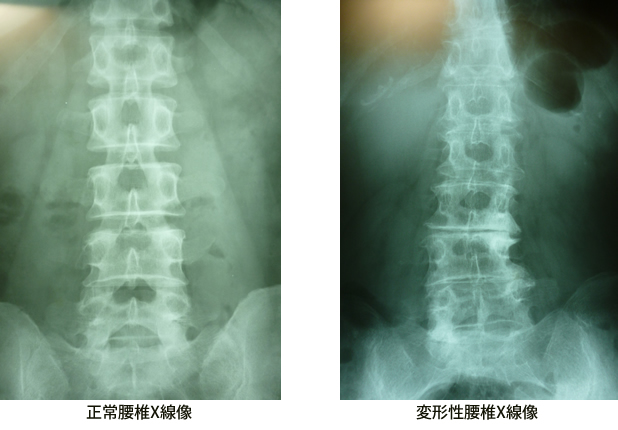

<変形性腰痛症>

40年近く放射線科で腰椎のX線撮影、CT、あらゆる検査を担当して来ましたが50歳近くになると全ての患者さんは何らかの骨の変形、軟骨の狭小化と過骨???が見られます。やがて脊柱間狭窄症に移行し歩くのもままならない患者さんも見受けられます。

変形性腰椎症

腰椎4番にスベリ症が見られます。

腰椎5番は椎間板の狭窄と過骨化が見られます。

腰椎の変形は年月と共に誰にでも起きることです。

必要以上に心配する事はありません。

治療しながら上手に腰痛と付き合うことです。